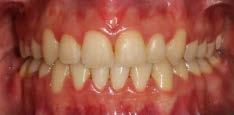

El tratamiento se terminó a los 2 años y 3 meses, en los estudios extraorales finales se ve la coincidencia de la línea media dental superior, con la línea media dental, la exposición dental que muestra la sonrisa (Figura 5), el cambio que se obtuvo en el perfil debido a la retracción del sector anterior.

Estudios intraorales finales

Se observa el cierre de la mordida, la línea media inferior desviada 1 mm hacia la derecha respecto a la línea

media superior, el overjet de 2 mm y un overbite del 20%, (Figura 6).

Se obtuvo clase I molar bilateral y clase I canina bilateral (Figura 7).

En las fotografías oclusales observamos la forma de arco oval, la solución del apiñamiento y el cierre de la mordida abierta. (Figura 8)